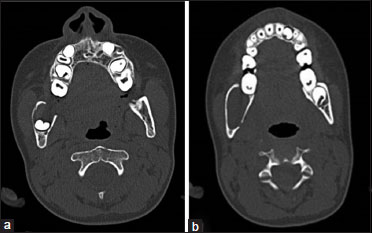

Panoramic CT section [Figure 3] and sagittal CT section [Figure 4] showed hypodense area of size 2.5 cm × 3 cm surrounding the developing tooth bud of 47. Axial CT section [Figure 5]a showed tooth within the hypodense area, and axial CT section [Figure 5]b showed buccal cortical plate expansion with breakdown of lingual cortical plate.

| Figure.5:(a) Axial computed tomography section showing tooth within the hypodense area (b) Axial computed tomography section showing buccal cortical plate expansion with breakdown of lingual cortical plate